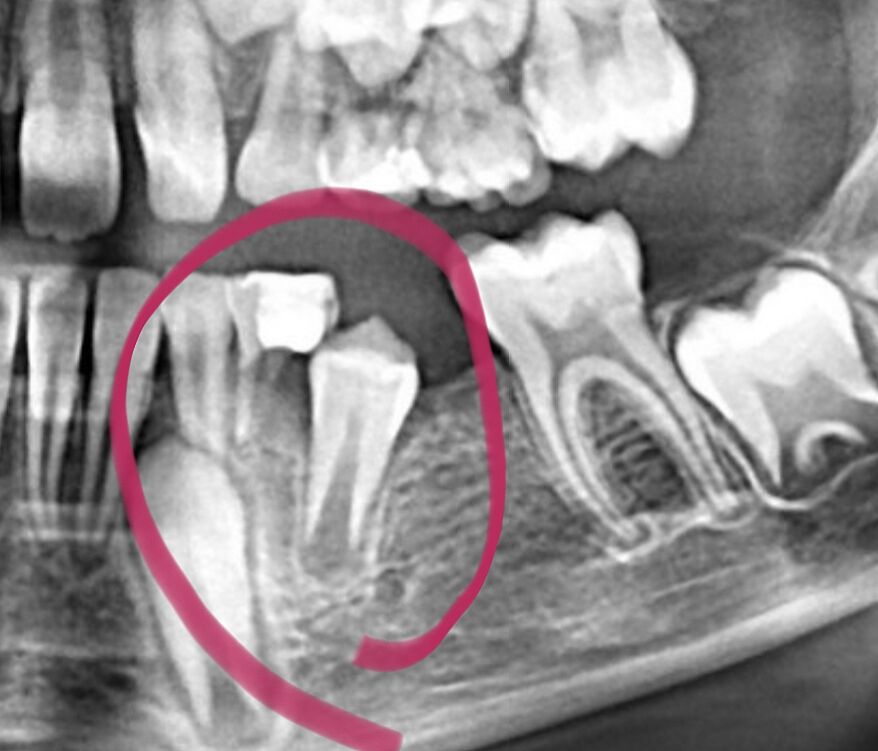

У дитини немає зачатку п´ятого зуба.

Сину 9, пішли лікувати зуби, у лікаря з´явились сумніви що до п´ятірки, зробили знімок, а там немає зачатку, покликала ортодонта, вона сказала, що можна поставити розпорку, щоб подвтнути його на своє місце, а в майбутньому імплант. Четвертий видалили, але зуб посередині, чоловік каже, що може не треба, він вже виріс, прийняв своє місце, може хай так і буде посередині. Я щось не знаю, чи ще консультуватись з лікарем?

Делали панорамный снимок, есть там. Эх если б знали берегли б молочную пятёрку